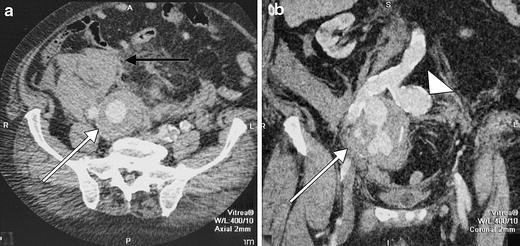

Ruptured aneurysms of the internal iliac artery (IIA) are rare and challenging to treat surgically. Due to their anatomic location they are difficult to operate on and perioperative morbidity is high. An endovascular approach can be helpful. We recently treated a patient with a ruptured IIA aneurysm in the interventional radiology suite with embolization of the side-branch of the IIA and placement of a covered stent in the ipsilateral common and external iliac arteries. A suitable stent-graft was not available initially and had to be brought in from elsewhere. An angioplasty balloon was temporarily placed across the ostium of the IIA to obtain hemostasis. Two hours later, the procedure was finished by placing the stent-graft.